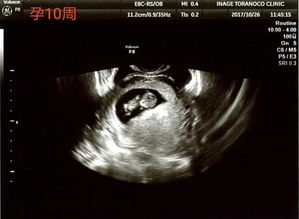

在进行系统B超检查时,孕妇需要提前预约。一般来说,24周的系统B超检查可以在22-28周之间进行,最佳时间为24周左右。预约时,孕妇应提供详细的个人信息和孕周,以便医生安排合适的检查时间。

在检查过程中,孕妇需要保持放松,避免紧张情绪对胎儿造成影响。此外,孕妇应穿着宽松的衣物,以便于医生进行B超检查。